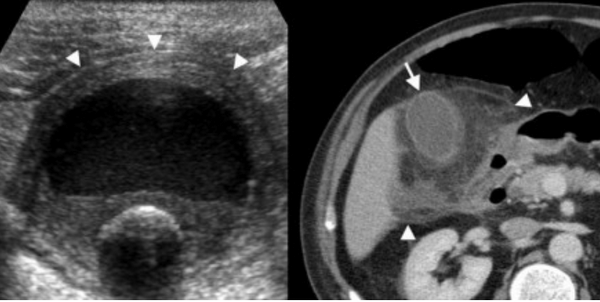

(Левый) Пример неполного кальциноза: у женщины 67 лет, жалующейся на боли в правом верхнем квадранте живота после еды определяются отдельные гиперэхогенные очаги передней и задней стенок желчного пузыря, отбрасывающие неоднородную тень.

(Правый) Пример неполного кальциноза: у мужчины 61 года в стенке желчного пузыря визуализируются точечные кальцинаты. Выявленные при патологоанатомическом исследовании конкременты не визуализируются.

Острый калькулезный холецистит. После контрастного усиления визуализируется растянутый желчный пузырь (белые наконечники) со слегка утолщенной стенкой. Визуализируется камень в шейки желчного пузыря (белая стрелка).

Сверху изображения пациента 62 лет с калькулезным холециститом. На УЗИ визуализируется стенки желчного пузыря растянутые, с субсерозным отеком (указано белыми стрелками) и в просвете желчного пузыря камень и взвесь. На КТ визуализируется переход воспалительного процесса с желчного пузыря на соседние ткани (перихолецистит).

УЗИ (слева) и КТ (справа) желчного пузыря. На УЗИ ярко выраженное утолщение стенки желчного пузыря (указаны белыми стрелками). Множественные камни в просвете желчного пузыря (указано стрелкой). Компьютерная томография с контрастным усилением. На КТ визуализируются утолщение стенки с внутристеночными гиподенсными включениями. На КТ также выявлено, что процесс распространился на печень (указано стрелкой).